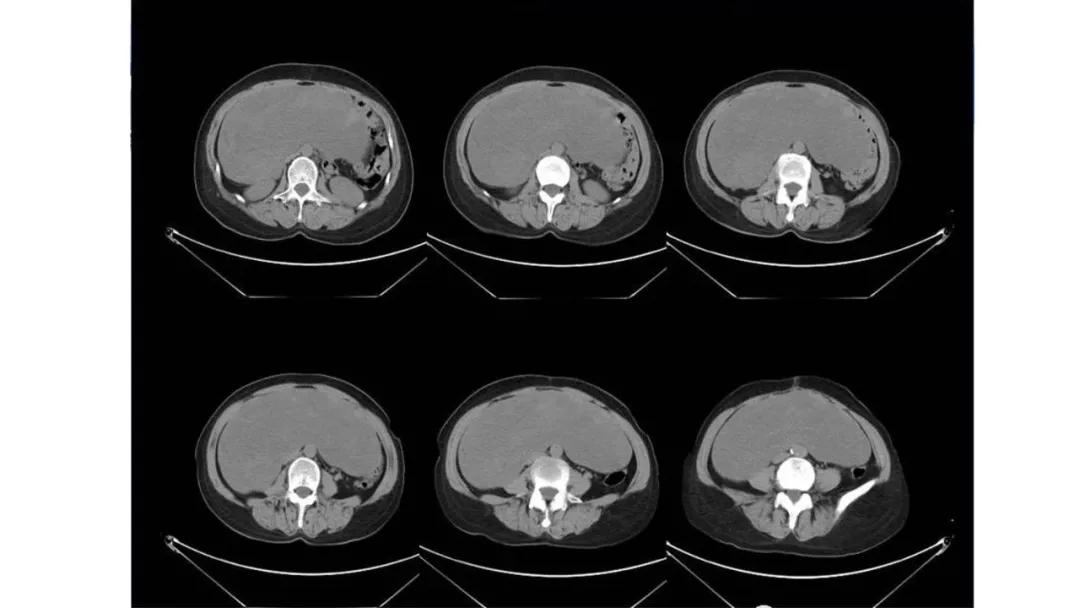

病例4 女,32岁,以“月经量增多伴经期延长半年。”

缘于患者入院前半年无明显诱因出现月经量增多,卫生巾由原来3包余增至5包不等,伴血块,经期由原来7天延长至10-15天不等,无痛经,无月经周期改变,无阴道异常排液,无畏冷、发热,无头晕、乏力等不适,未重视,未诊治。期间症状持续。2月前就诊我院,查彩超示:“子宫体大小约5.7*5.3*4.6cm,内膜厚约0.6cm,回声不均,左卵巢旁探及大小约4.2*3.5cm低回声区。”建议治疗,患者及家属表示考虑。期间症状持续,今就诊我科门诊,要求住院手术治疗,无腹痛等不适,门诊拟“卵巢囊肿”收住入院。既往史:2007年剖宫产一次,术顺。月经史:15 7/25 lmp2018.05.14,量中,无痛经。婚育史:已婚,1-0-3-1,末孕2007年剖宫产娩一男婴,儿子及丈夫体健。个人史、家族史均无特殊。

CA125 335.5(U/mL);2018-05-30 彩超:子宫宫体大小约5.6㎝×6.3㎝×4.9㎝,形态正常,宫壁回声欠均,内膜厚约1.8cm,回声不均。CDFI:子宫内未见明显异常彩色血流信号。左附件区探及一混合回声团块,大小约9.8㎝×7.9㎝,CDFI:其实性部分可见少许彩色血流信号。右附件区未见明显包块回声。

病理:卵巢子宫内膜样癌